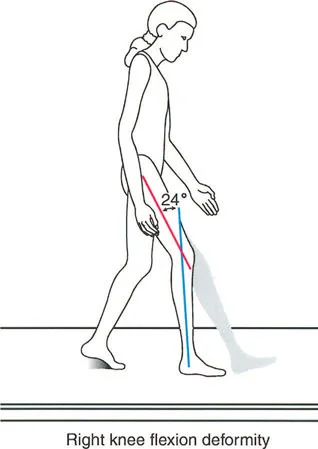

لنأخذ على سبيل المثال، تشوه الانحناء الأمامي (procurvatum) في الجزء القريب من عظم الساق. نظرًا لأن قمة التشوه أمامية، يميل سطح عظم الساق القريب (tibial plateau) إلى الخلف (مما يؤدي إلى زيادة في زاوية الظنبوب القريب الخلفية، أو pPTA). عندما يحاول المريض الوقوف مستقيمًا، قد تتمدد مفصل الركبة بالكامل تشريحيًا (0 درجات بين عظم الفخذ البعيد وعظم الساق القريب)، ولكن نظرًا لأن جدل الساق مقوس إلى الأمام، يظل الطرف الكلي مثنيًا بالنسبة للمحور الميكانيكي.

يظهر هذا سريريًا على شكل تشوه انثناء ثابت (Fixed Flexion Deformity - FFD) في الركبة. على عكس الجزء البعيد من عظم الساق، فإن مفصل الركبة لديه قدرة محدودة جدًا على فرط التمدد للتعويض عن هذا. نظرًا لأن الساق لا يمكن أن تستقيم بالكامل بالنسبة للأرض، لا يمكن للمريض تحقيق ملامسة كعب طبيعية أثناء الاتصال الأولي. بدلاً من ذلك، يظهرون "قدم مسطحة" أو "ملامسة أصبع القدم" عند الاتصال الأولي، مما يقلل بشكل كبير من امتصاص الصدمات، ويزيد من إجهاد العضلة الرباعية، ويقلل بشكل كبير من طول الخطوة في الجانب المصاب.

التشوه الأساسي مقابل التشوه الديناميكي الثانوي

عند تقييم المريض في العيادة، يجب على جراح الترميم، مثل الأستاذ الدكتور محمد هطيف في صنعاء، أن يعمل كمحقق ميكانيكي حيوي لفصل التشوه الهيكلي الأساسي عن التشوه التعويضي (الديناميكي) الثانوي. إن معالجة التعويض مع تجاهل السبب الجذري هو وصفة مضمونة للفشل الجراحي.

على سبيل المثال، مريض يعاني من انكماش ثابت في الكاحل (equinus contracture) (تشوه أساسي) لا يمكنه تحقيق قدم مستوية بشكل طبيعي. لوضع الكعب على الأرض، سيدفع الركبة إلى فرط تمدد شديد أثناء مرحلة الوقوف (تشوه ديناميكي ثانوي). بعد عقد من المشي بهذه الطريقة، سيحضر المريض إلى العيادة شاكيًا من ألم شديد في الجزء الأمامي من الركبة، وليس ألمًا في الكاحل.

غالبًا ما يكشف التصوير بالرنين المغناطيسي عن تمزقات تنكسية أمامية في الغضروف الهلالي وآفات غضروفية متقابلة في المفصل الظنبوبي الفخذي الأمامي ناتجة عن الانحشار الأمامي المتكرر للركبة المفرطة التمدد. إذا عالج الجراح الركبة فقط (مثل استئصال الغضروف الهلالي أو قطع عظم الساق القريب)، فستفشل الجراحة لأن المحرك الأساسي للمرض - انكماش الكاحل - قد تم تجاهله.